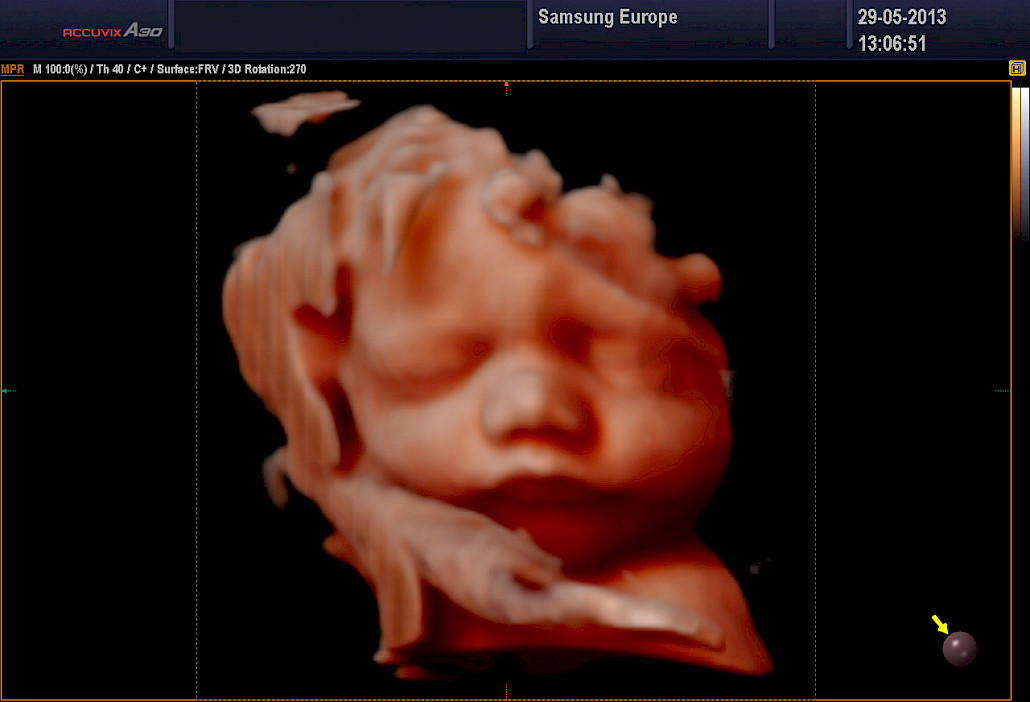

Ehdottomasti molemmat! 3D-tekniikalla tuotetaan staattista neulanterävää kolmiulotteista kuvaa. Se soveltuu sikiön kuvaamiseen, kun halutaan mahdollisimman tarkkaa ja korkealaatuista kuvaa. 4D-tekniikka on tarkoitettu erityisesti sikiön liikkuvaan ja kolmiulotteiseen kuvaamiseen.

3D ja 4D-tekniikat soveltuvat erityisen hyvin sikiön kasvojen anatomian tutkimiseen. Tutkimuksessa poissuljetaan mahdollinen huulihalkio ja kasvojen profiilissa esiintyvät muut poikkeamat, kuten liian pieni leuka. Samalla selvitetään korvien anatomia ja niiden sijainti. Tekniikan avulla selvitetään raajojen asennot, sekä sormien ja varpaiden lukumäärä ja niiden liikkuvuus. Lisäksi tutkitaan koko selkärangan rakenne ja suljetaan pois poikkeamat, kuten puuttuvat lapa- tai olkaluut.

4D-tutkimukset voidaan tehdään koska tahansa raskauden aikana. Sikiön rakenne voidaan selvittää kuitenkin parhaiten raskausviikoilla 19-30. Sikiön kasvonpiirteet näkyvät parhaiten raskausviikoilla 22-28. Niukka lapsiveden määrä, epäedullinen sikiön asento, äidin ylipaino tai paksut vatsanpeitteet saattavat vaikuttaa 4D-kuvien laatuun, mutta ne harvoin estävät tyydyttävän arvion saamista sikiön anatomiasta.

Sikiöstä otetut kolmiulotteiset kuvat ovat erittäin tarkkoja ja havainnollistavia – suorastaan kauniita. Kuvauksiin voi tulla millä tahansa raskausviikolla. Tutkimusta ei tarvitse pelätä ja tulevan lapsen isä ja sisarukset ovat myös lämpimästi tervetulleita. Tilanne on usein ikimuistoinen ja ainutkertainen kokemus koko perheelle.